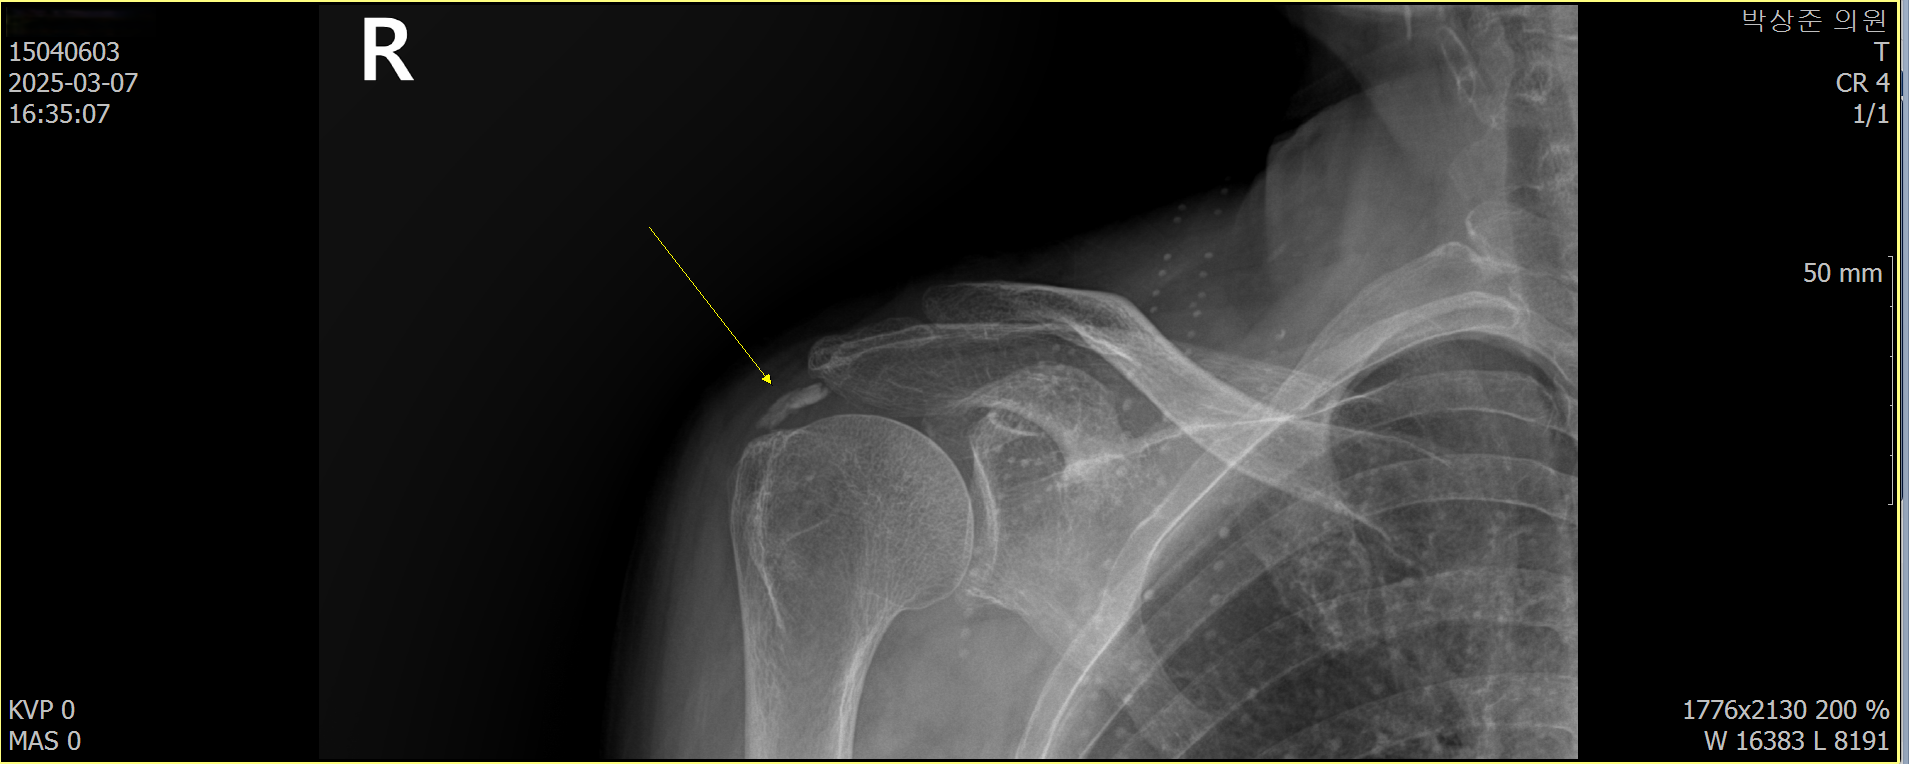

석회성 건염의 경우 사이즈가 조금만 커도 x-ray에서 쉽게 진단이 가능합니다. 이 환자분의 경우 우측 어깨에 사이즈가 꽤 커다란 석회가 관찰되고 있었습니다.

나 : 보시다시피 여기 이렇게 큰 석회가 들어 있네요. 이전에도 이정도로 보였나요?

환자 : 정확히는 기억 안나지만... 비슷한거 같은데...

나 : 그럼 체외 충격파만으로는 치료가 안되는 케이스네요.

위에 비포 & 애프터 사진에서 보다시피 처음보이던 커다란 석회가 5회의 치료동안 약 90% 가량 사라진것을 확인할 수 있습니다.